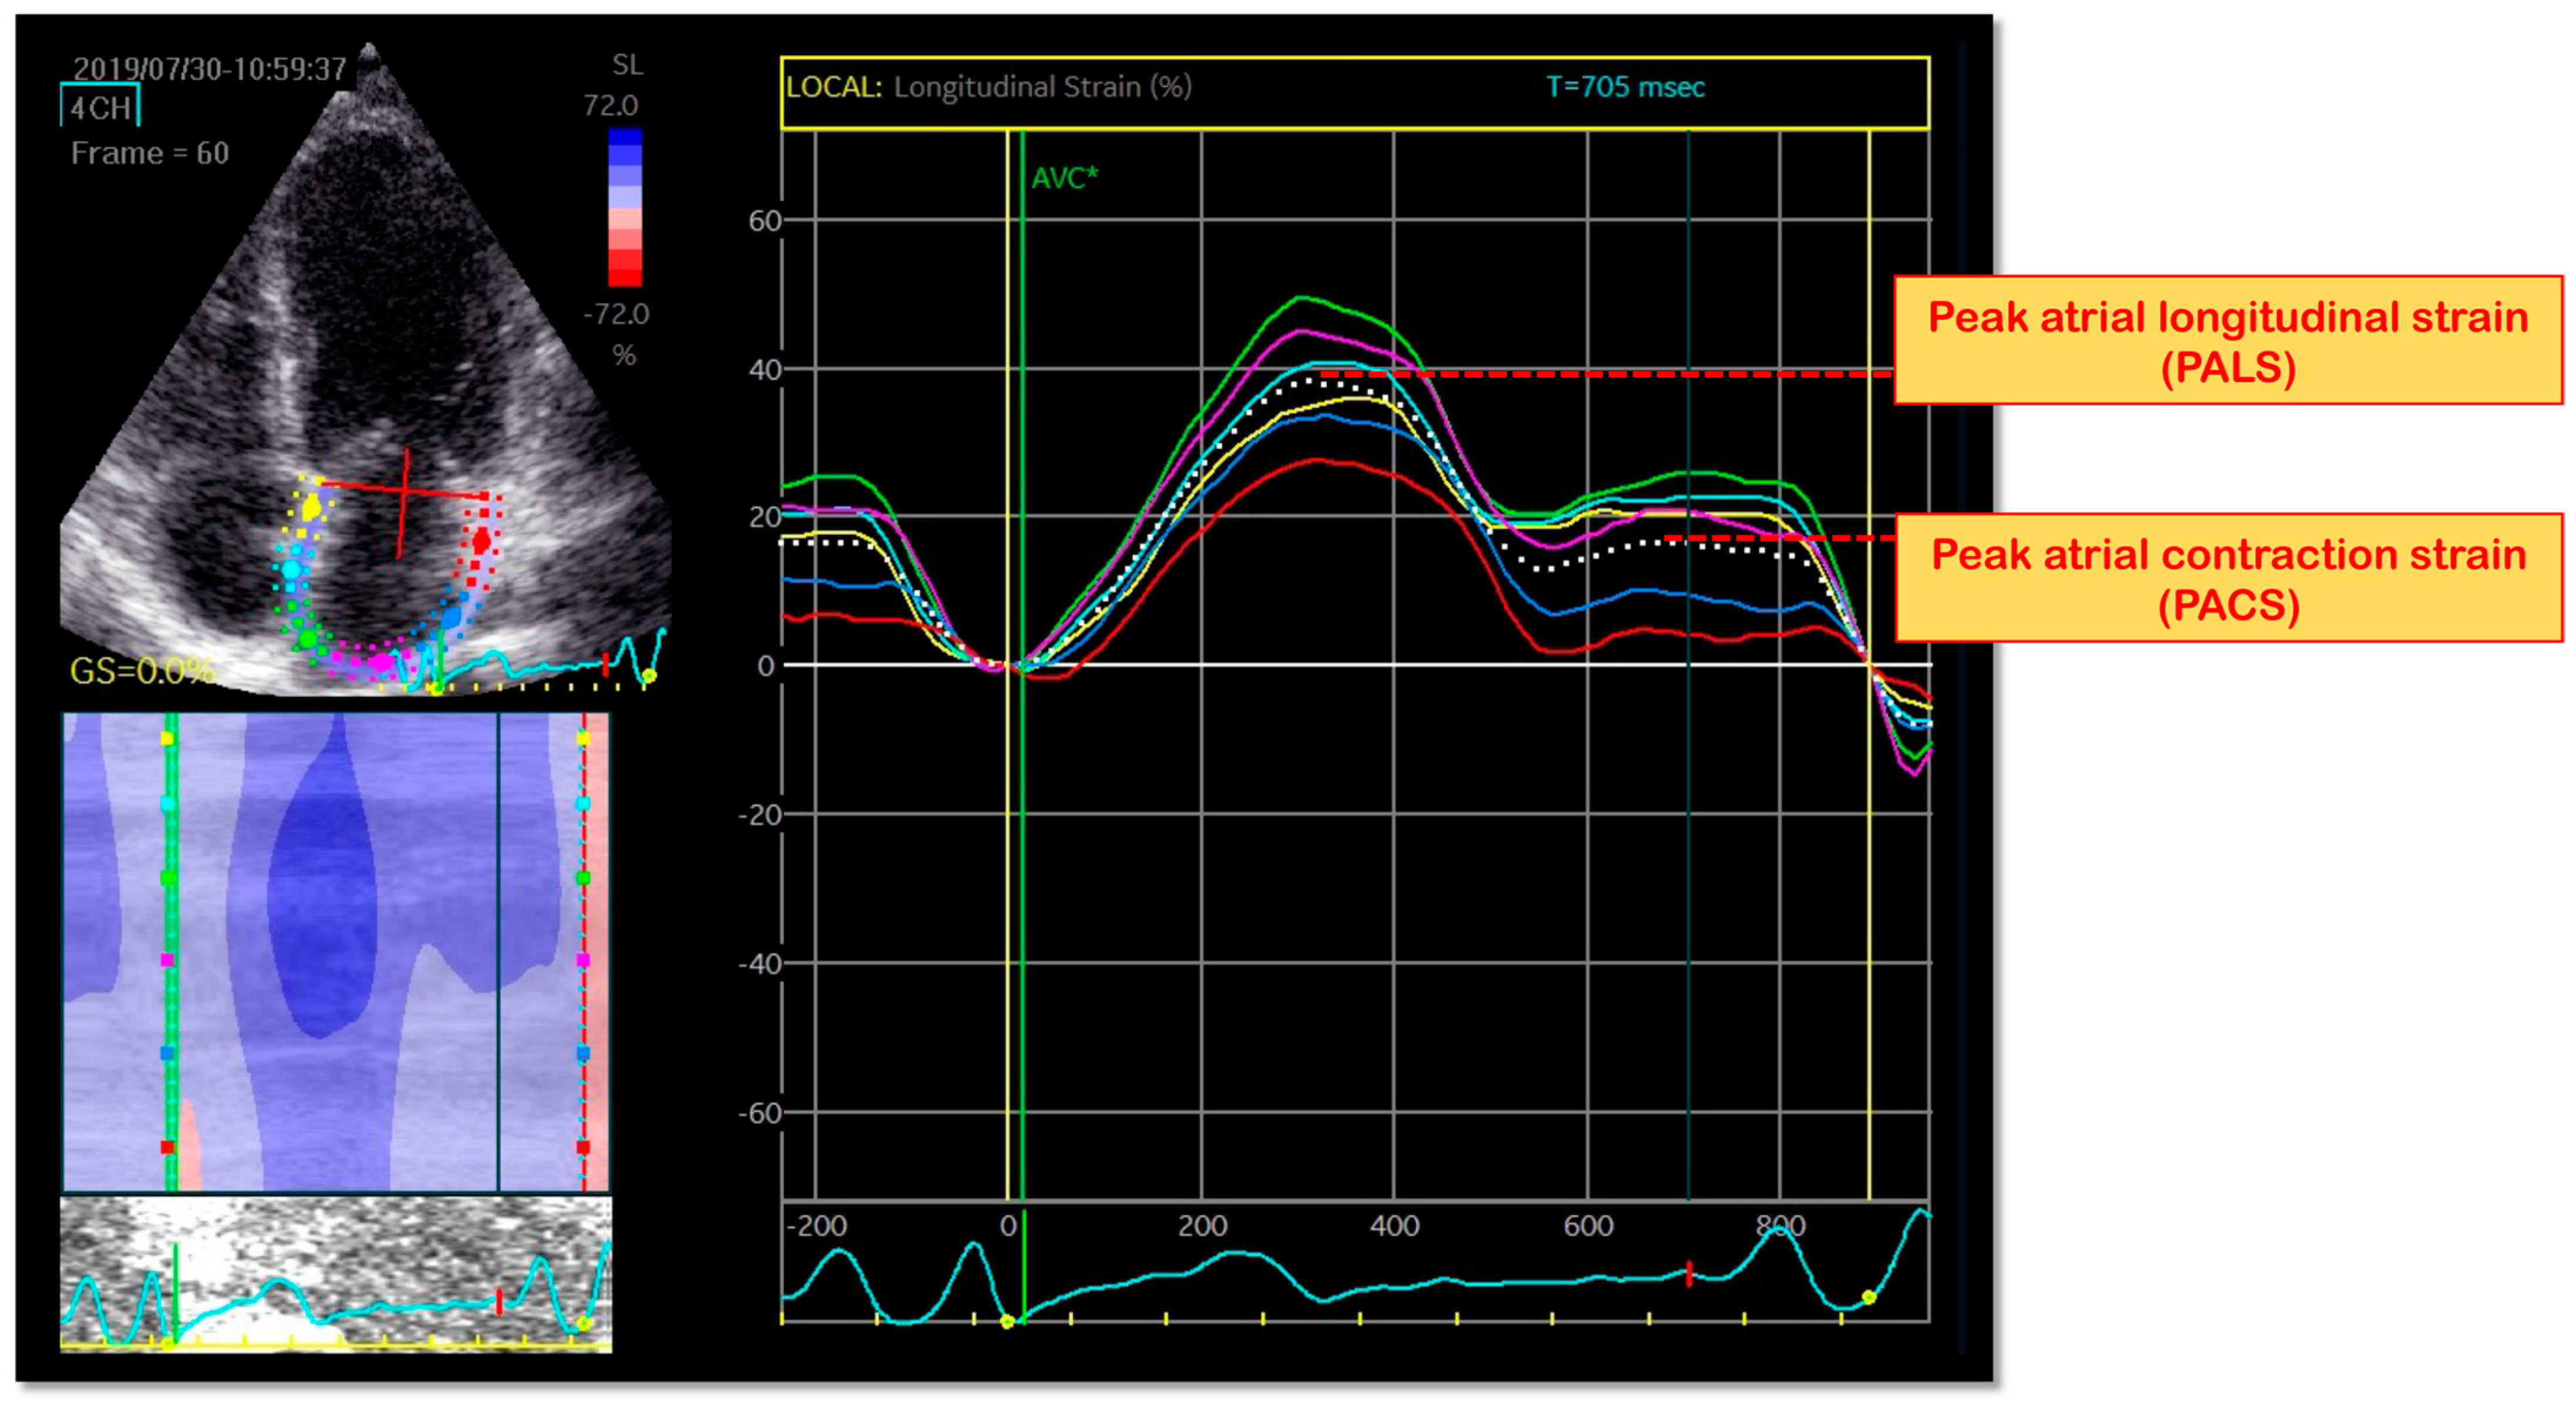

6. LA Longitudinal Myocardial Intrinsic Function by STE